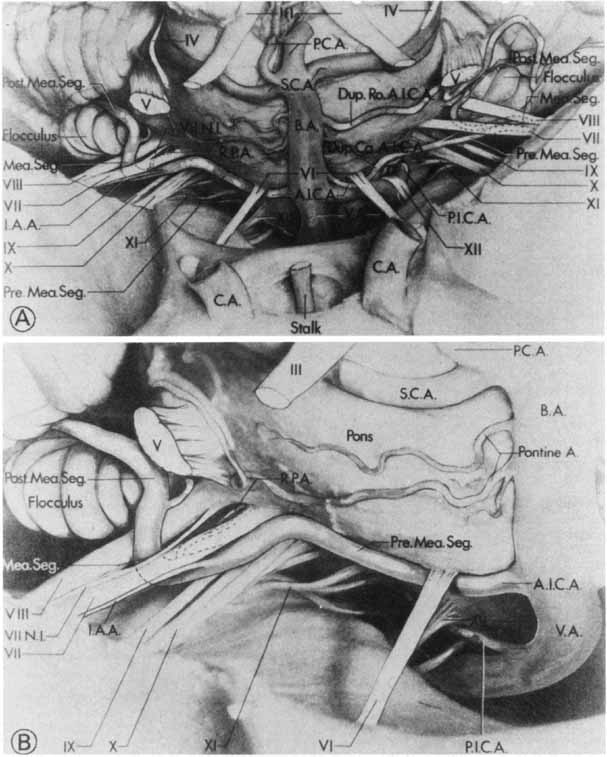

the facial vestibulocochlear nerve complex. Neurosurgery 6:483, 1980. 11. Guerrier Y: Surgical anatomy, particularly vascular supply of the facial nerve. In Fisch U (ed): Facial Nerve Surgery. Birmingham: Aesculapius Publishing Co., 1977: 12–23 12. Davis RA, Anson BJ, Puddinger JM, Kurth RE: Surgical anatomy of the facial nerve and parotid gland based upon a study